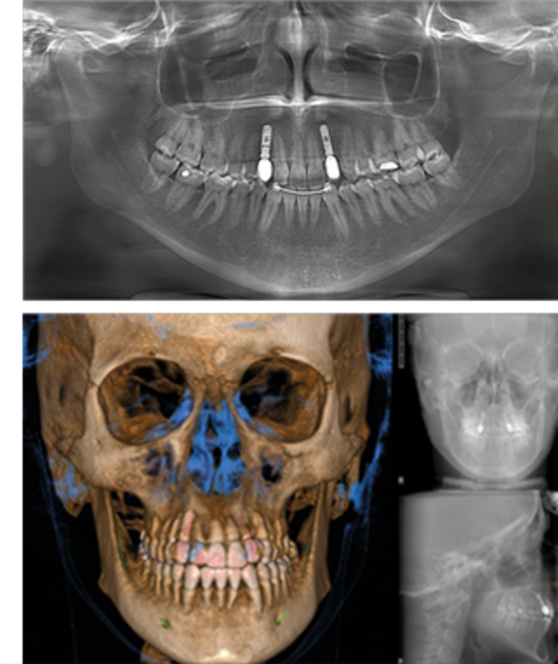

LA CBCT HÍBRIDA MÁS COMPLETA PARA EL IMAGING 2D/3D. IMÁGENES EN ALTA DEFINICIÓN QUE CAPTURAN LOS MÁS MÍNIMOS DETALLES.

GO 2D/3D/CEPH ofrece imágenes de alta calidad en un solo dispositivo compacto, satisfaciendo una amplia gama de necesidades diagnósticas clínicas.

Tres protocolos de examen preprogramados permiten identificar con eficacia el modo de adquisición más indicados.

GiANO HR ha sido diseñado para ofrecer el mejor confort y la máxima seguridad al paciente en cualquier situación, gracias a su elevada ergonomía y a sus tiempos de emisión extraordinariamente reducidos.